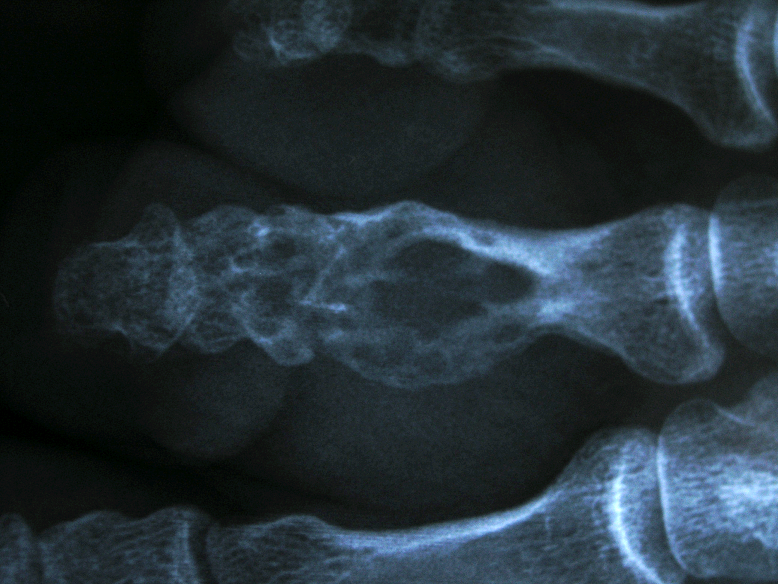

患者,男,30岁,右足第三趾近节腱鞘巨细胞瘤并骨破坏,行肿瘤切刮除及异体骨植骨术。

术前X线片